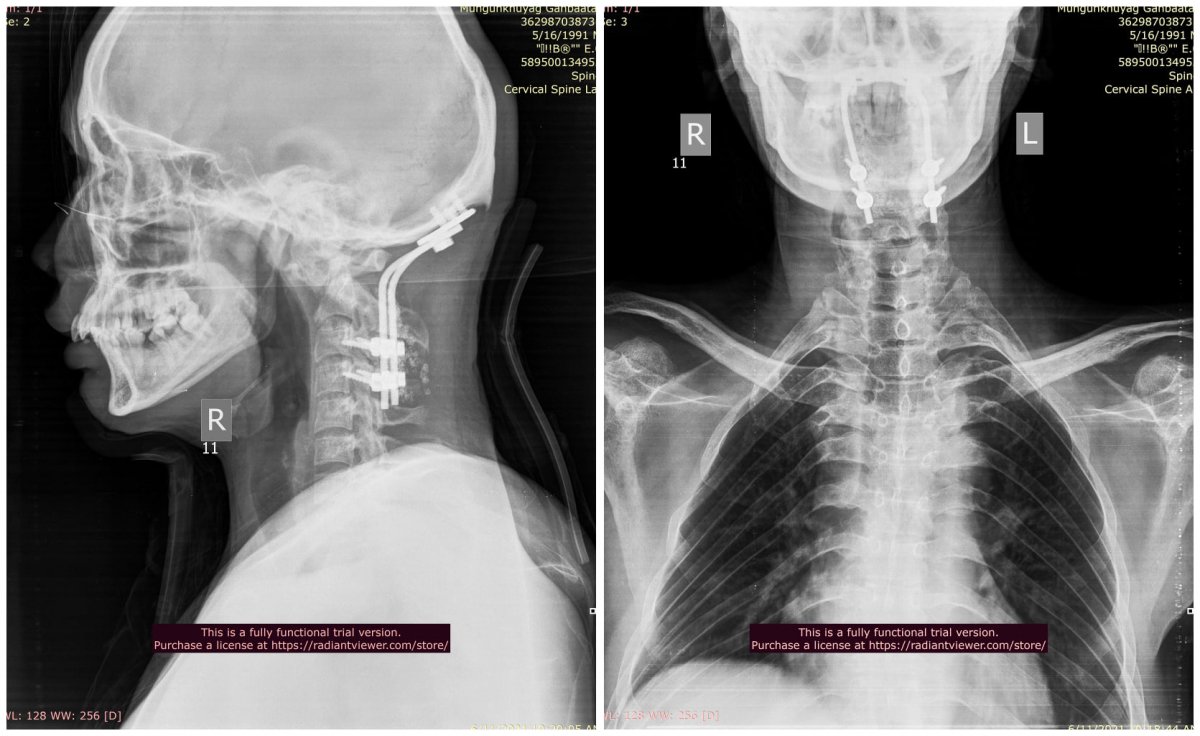

Гэмтэл Согог Судлалын Үндэсний төвийн зөвлөх эмч Ж.Оюунтөгс, Л.Бат-Эрдэнэ тасгийн эрхлэгчтэй, Б.Баттөгс ахлагчтай Хүзүү нурууны гэмтэл согогийн тасгийн хамт олон Монголд анх удаа хүзүүний нугалмын хугарал мултралыг арын хүрцээр дагз ястай хамт бэхлэх мэс заслыг амжилттай хийлээ.